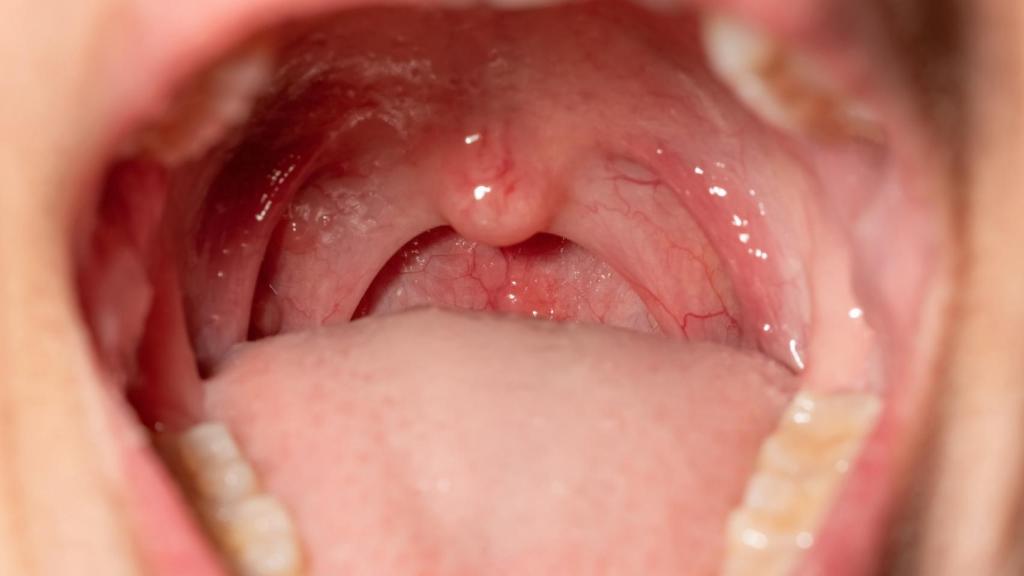

La extirpación de las amígdalas llegó a ser muy frecuente hace unas décadas.

La extirpación de las amígdalas llegó a ser muy frecuente hace unas décadas. iStock